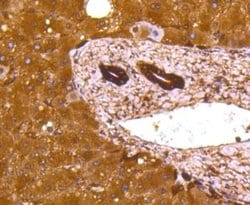

Lactate Dehydrogenase A/LDHA Monoclonal specifically detects Lactate Dehydrogenase A/LDHA in Human, Mouse, Rat, Zebrafish samples. It is validated for Western Blot, Flow Cytometry, Immunohistochemistry, Immunocytochemistry/Immunofluorescence, Immunoprecipitation, Immunohistochemistry-Paraffin.Specifications

| Western Blot 1:1000-1:5000, Flow Cytometry 1:50-1:100, Immunohistochemistry, Immunocytochemistry/Immunofluorescence 1:50-1:200, Immunoprecipitation, Immunohistochemistry-Paraffin 1:200-1:2000 | |